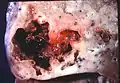

Image de pathologie d'un abcès pulmonaire.